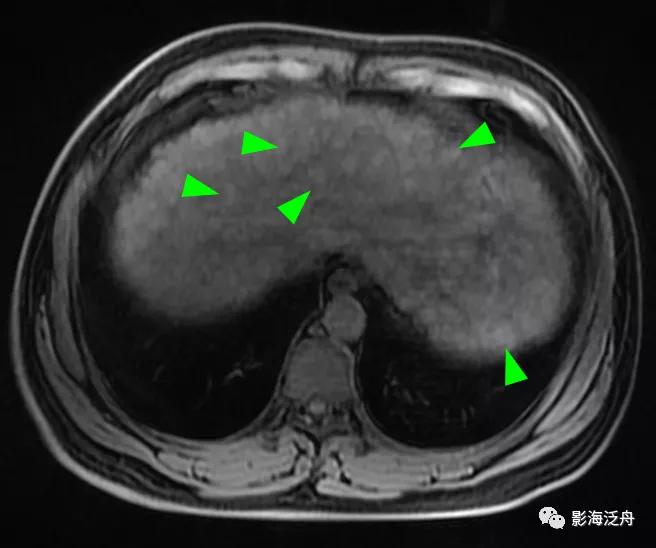

一例比较典型的肝硬化病例:T1WI上呈均匀稍高信号的再生结节(绿箭头)遍布全肝,再生结节在T2WI上呈明显低信号,这种低信号也是由于铁质沉积造成的,再生结节周围的纤维分隔因炎症浸润而呈高信号(红箭头)。